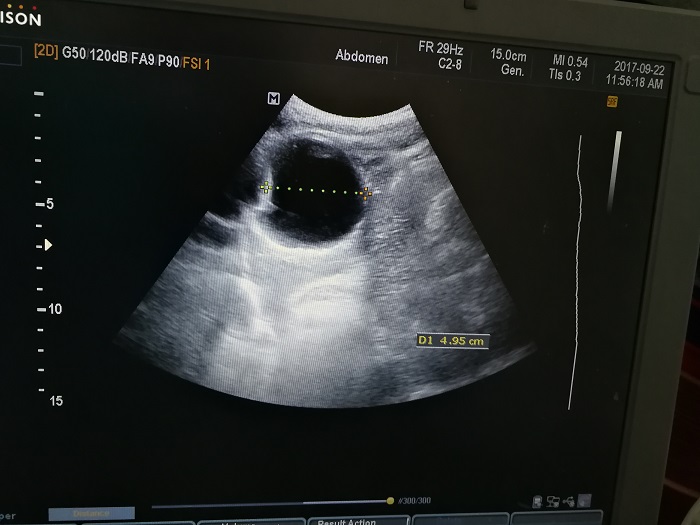

扎西(化名),男,15歲,包蟲病篩查陽性,牧區(qū)孩子,家里有牦牛20頭、羊200只,狗1條,牛羊自家屠宰,飲用河水。

●革吉縣初級中學(xué)篩查點 · B超現(xiàn)場圖片

除了包蟲病篩查外,連續(xù)三天的學(xué)校體檢我醫(yī)療隊發(fā)現(xiàn)腎積水、腎囊腫、腎結(jié)石的學(xué)生患者較多,我們將體檢到的相關(guān)臟器疾病同時間反饋給了班主任,讓他們密切觀察病情,及時通知家長。劉冬梅醫(yī)生建議,學(xué)校要組織學(xué)生多飲水,同時多加觀察本地水質(zhì)情況。

本次篩查,革吉縣初級中學(xué)共篩查學(xué)生498例,陽性3例,疑似2例。